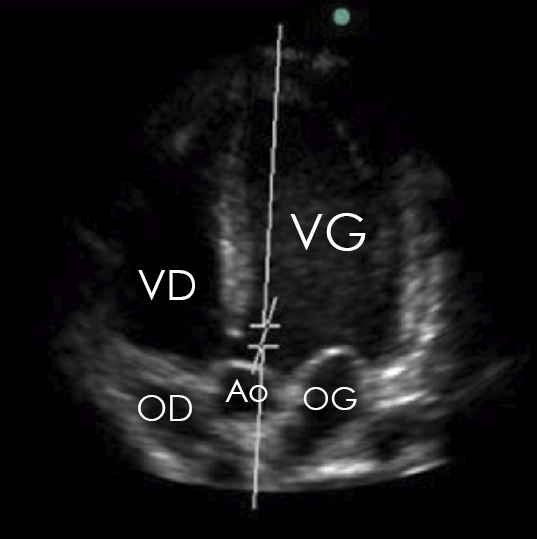

Figure 1 (Elon Zerah, La Revue du Praticien)

Une ETT se réalise en plaçant le patient en décubitus latéral gauche pour rapprocher le cœur de la paroi thoracique et augmenter l’échogénicité.

On distingue les 2 oreillettes, les 2 ventricules ainsi que l’aorte, il s’agit donc bien d’une coupe apicale 5 cavités.

On visualise la valve tricuspide entre l’oreillette droite et le ventriculaire droit, la valve mitrale entre l’oreillette gauche et le ventricule gauche, ainsi que la valve aortique dans la chambre de chasse ventriculaire gauche. La valve pulmonaire ne peut pas être visualisée sur cette coupe :

Il faut maîtriser les principales coupes à l’ETT pour identifier les différentes structures anatomiques intra-cardiaques : apicales 2, 3, 4 et 5 cavités, para-sternale grand axe et sous-costale.